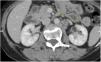

Se realizó tomografía computarizada (TC) de abdomen y pelvis simple, y contrastada con cortes axiales y reformateos multiplanares (fig. 1).

En esta se halla las asas del intestino delgado distendido con aire y líquido neutro, con engrosamiento mural concéntrico que realza homogéneamente (sin patrón de estratificación), a nivel de íleon distal de hasta 21mm de espesor, que condiciona estrechamiento de la luz, aproximadamente del 70%, provocando dilatación retrograda de este. Colon con aire y material de residuo.

Se concluye el engrosamiento de las paredes del íleon distal con defecto obstructivo retrogrado y datos sospechosos de actividad metastásica hepática y ganglionar retroperitoneal paraaórtico, por lo que se debe considerar tumoración carcinoide. Se decide la realización de laparotomía exploradora con los siguientes hallazgos de tumor de intestino delgado a 210cm de ángulo de Treitz, y 160cm de la válvula ileocecal que ocluye el 80% de la luz intestinal provocando engrosamiento de la pared hasta 10cm, se realiza resección intestinal con 10cm de extensión proximal y distal de tejido sano, y también entero anastomosis término terminal. A la exploración hepática se identifican bordes lisos, sin palpar tumoraciones superficiales ni profundas. No se realiza exploración de retroperitoneo debido a la ausencia de abultamientos o alteraciones macroscópicas.